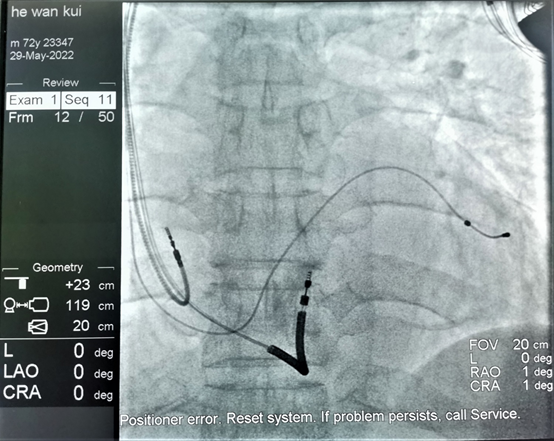

该病人患有心肌梗死多年,此后反复发生心力衰竭,近期多次因室速发作,就诊于各大医院,本次因室速发作不能终止收入我院心内二科,入院后予电复律将心律转复窦性心律。病人心脏彩超结果提示左心明显扩大,EF值为27%(正常值应大于50%),心电图提示QRS波群宽度为了144ms(提示有心脏收缩不同步的表现)。综合分析患者病情,认为患者为植入三腔ICD的适应征,既能预防因室速或室颤发作导致的猝死,又能通过双室起搏最大程度纠正患者的心力衰竭。手术过程非常顺利,右房、右室及左室电极分别成功植入了理想的起搏部位。该起搏器的植入将会有效的预防病人猝死的发生,并能最大程度的改善患者的心功能。